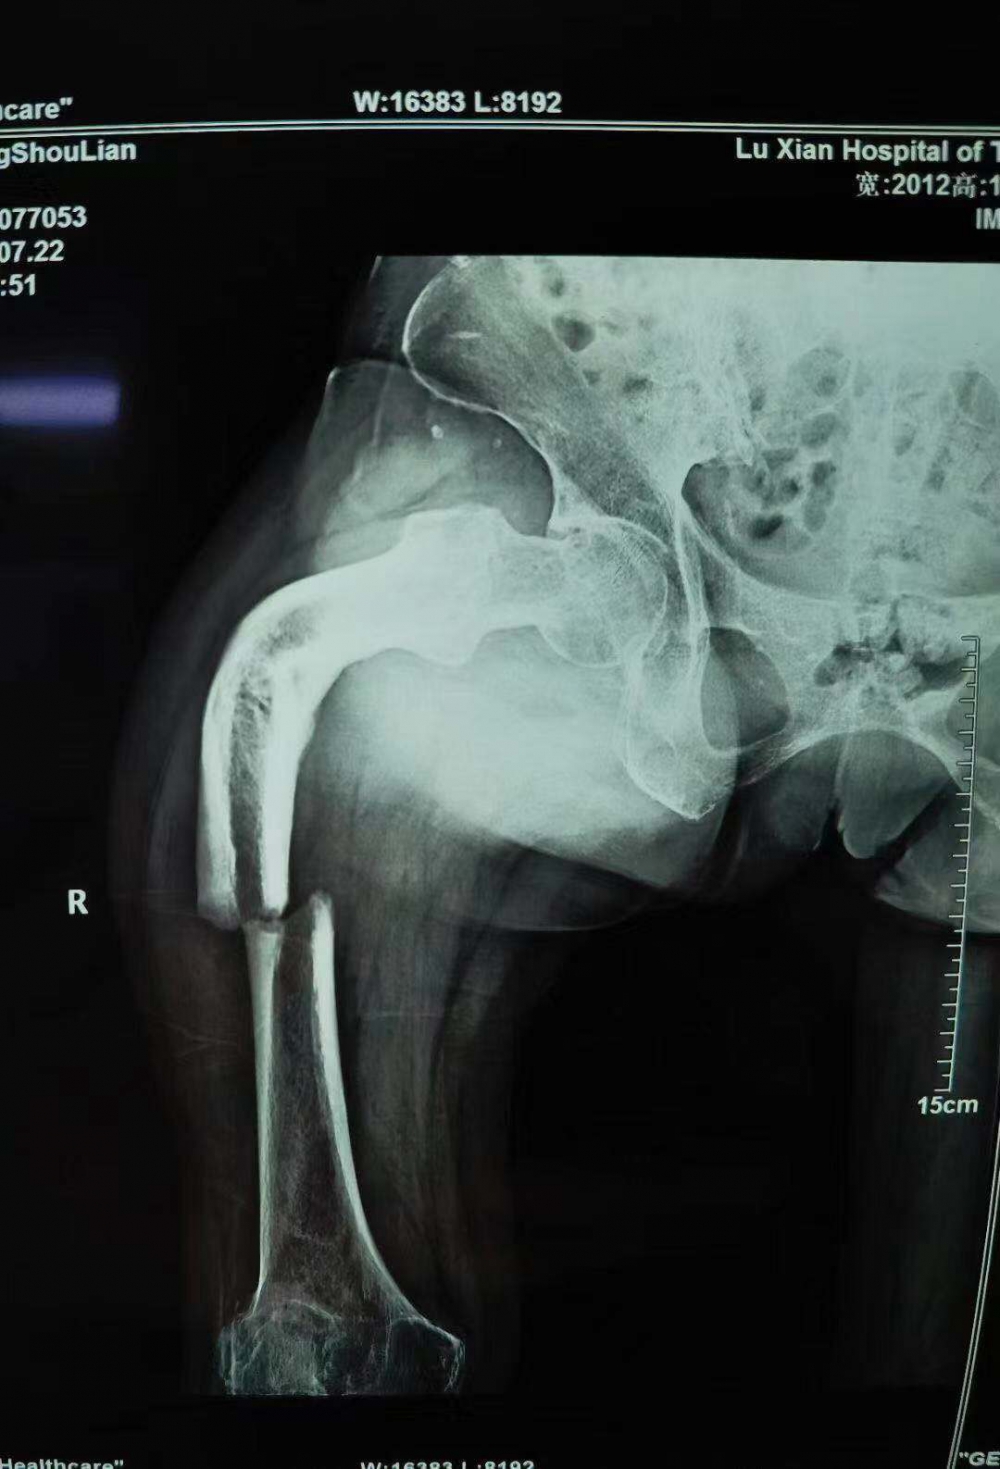

66岁的张守莲怎么也想不到,她最近在家门口坝子走路时不小心摔断了腿,却因祸得福,把自己三年来跛足的腿一并医治正常了。 (8月9日,张守莲康复锻炼走路) 树要发枝,腿也会发“新芽”? 张女士家住泸县云锦镇,常年在家务农。近日,她在家门口坝子走路时,不小心把大腿摔断,家人随即打了120,送到当地基层...